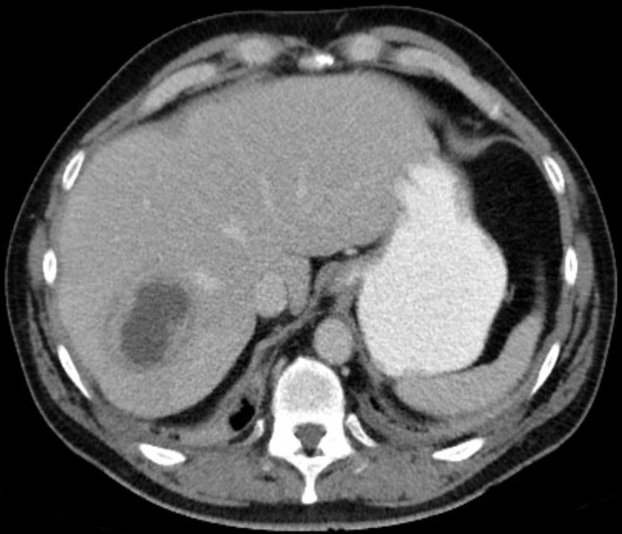

The patient had carcinoma of the bronchus.

CT scan of liver metastases. There are a large number of low density lesions in both lobes of the liver, which show enhancement around their edges.

LIVER METASTASIS

Imaging examination CT scan